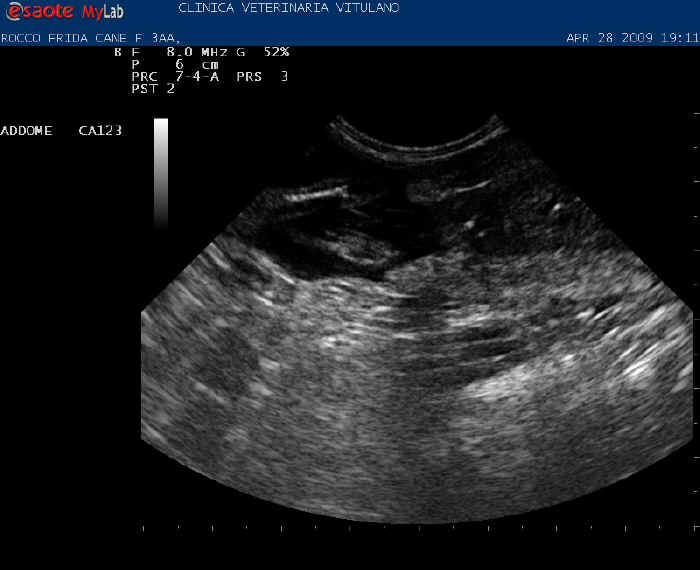

Immagine di una ecografia prima del parto

immagine di Valeria Rocco - Lupavaro